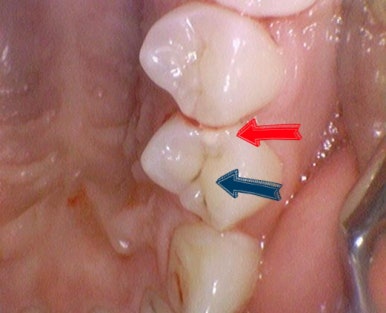

치아 사이 충치 제거 전(왼쪽) , 제거 중간(오른쪽)에 찍은 사진

위 사진과 같이 치아 사이 충치는 완전히 까맣게 보이지 않는 경우도 많아서

환자분들에게 충치가 있다고 하면 안보인다고 생각하실 수도 있는데요

경험많은 치과의사의 눈과 엑스레이로 체크하면

충치가 진단되기도 합니다.